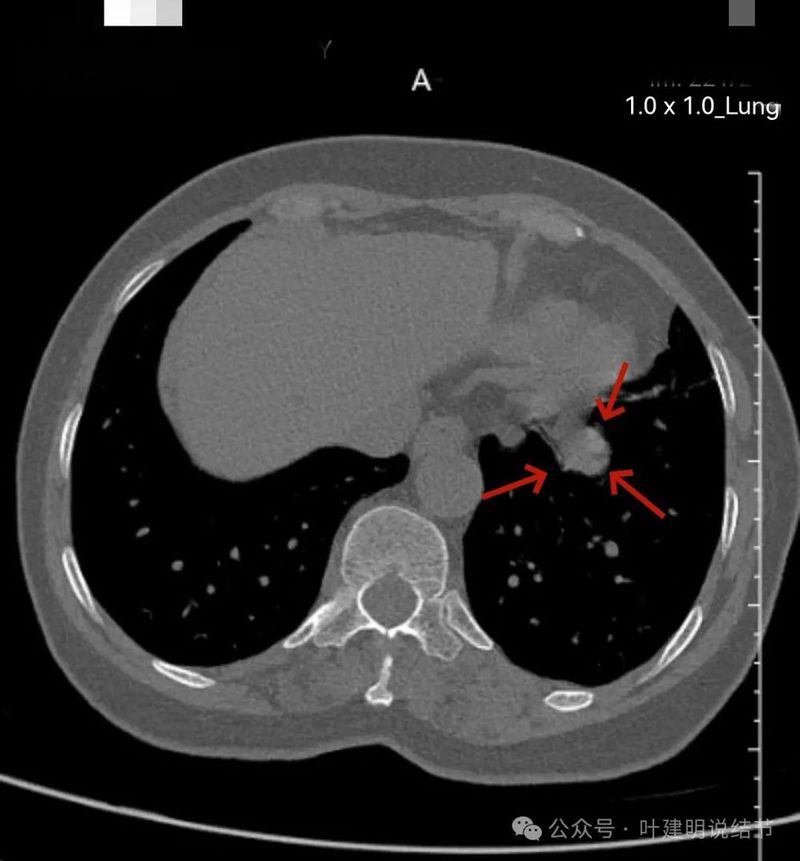

再看左下主病灶连续层面与重建影像:

冠状位见病灶与周围结构有间隙,说明不像炎性,如果是炎症,挨这么近,一般会搭牢的。

病灶表面不平,有浅分叶,与膈肌之间有间隙。

与膈肌之间间隙明显,病灶实性,膨胀性明显,边缘相对较为光滑。

感觉两处不同的中心,如果连续层面看,应该是病灶不平的关系,与膈肌间仍有间隙,密度是实性的。

纵隔窗见病灶实性密度,与膈肌间有低密度线状间隙。